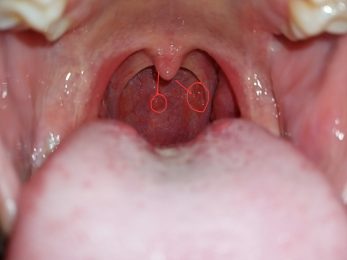

Viêm amidan hốc mủ là tình trạng viêm nhiễm amidan nghiêm trọng, gây ra các cơn đau họng dữ dội và khó chịu. Tuấn tôi...

Amidan có vai trò quan trọng trong hệ miễn dịch, nhưng khi bị viêm, người bệnh sẽ cảm thấy khó chịu, đau họng, thậm chí...